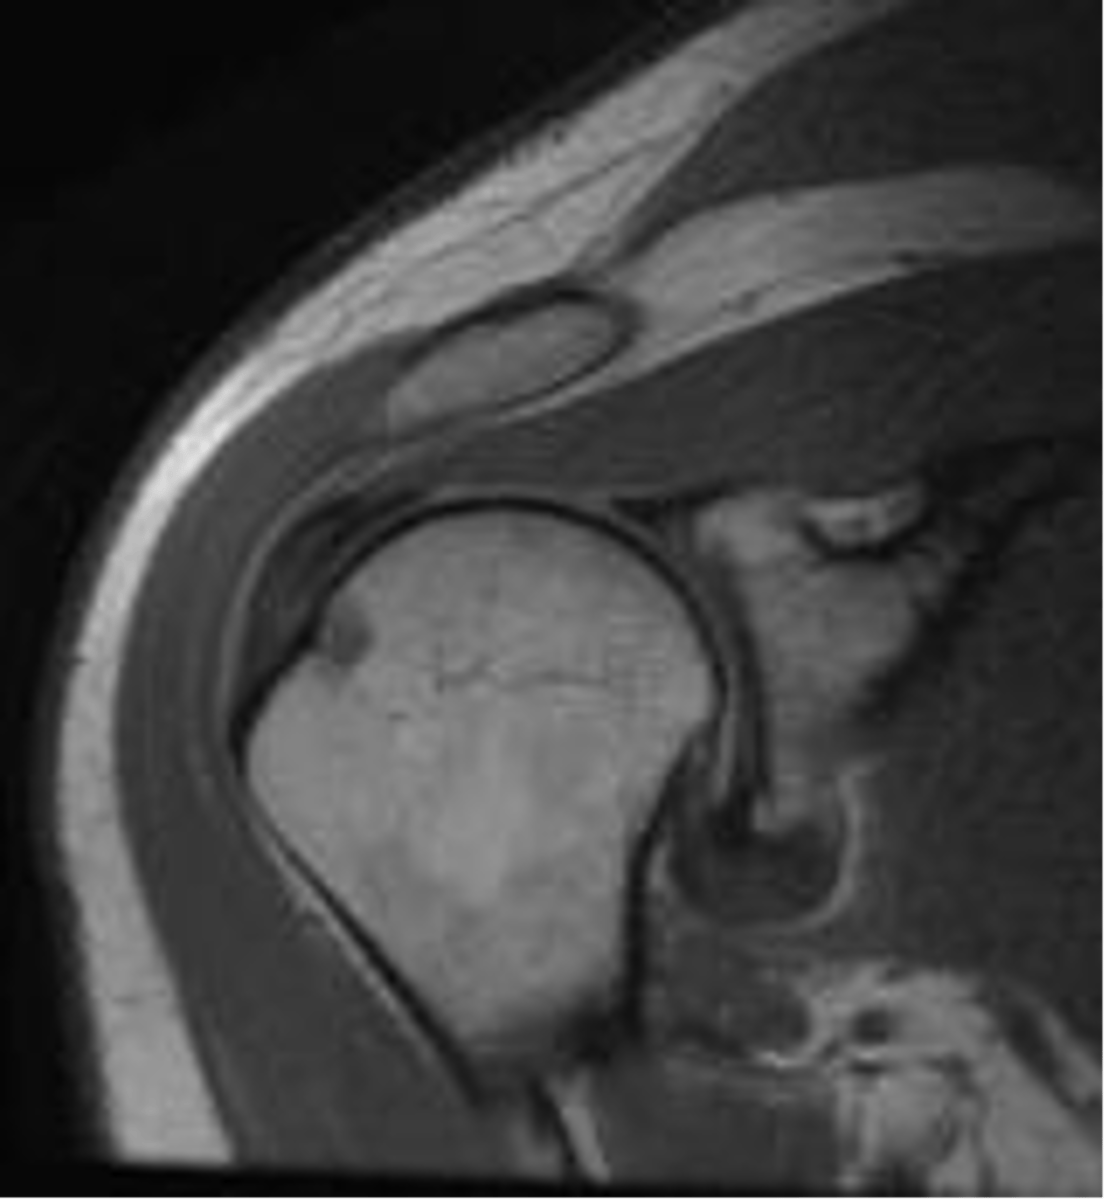

Full-thickness tear!!

- fluid (area of tear) in white

- retraction in red

- bucking in green

What is this image depicting w/ the rotator cuff? (hint: it is a T2 image)